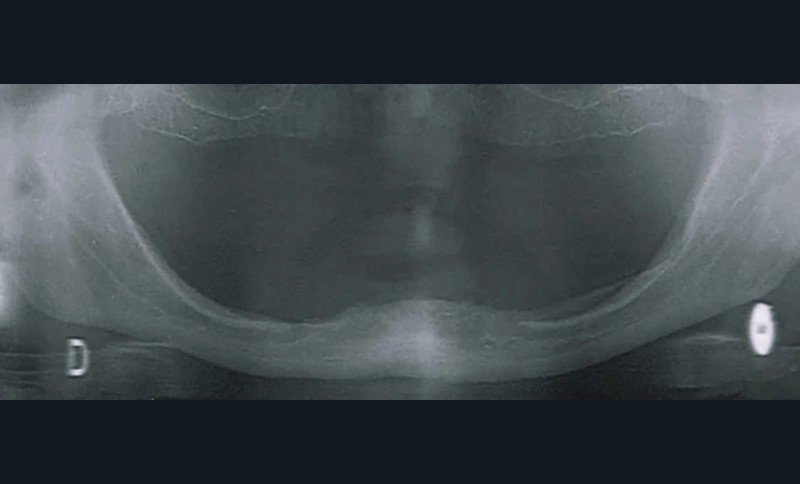

- Le terrain : pas de prothèse sur un terrain non préparé. L’examen clinique se fait à l’échelle du visage (soutien des tissus, de face et de profil) puis au niveau buccal. À ce stade, des régularisations de crêtes osseuses peuvent être indiquées. Dans le cas d’une gestion de tissus mous, cela peut passer par de la chirurgie et/ou par une mise en condition tissulaire avec une résine souple.